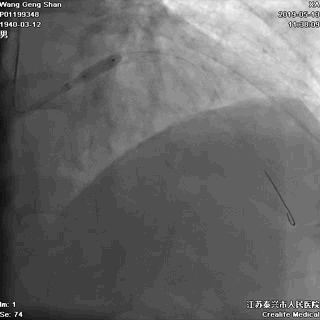

03 第一第二对角支保护

对角支导丝到位

左冠共计5根导丝

前降支近段支架植入后用非顺应性球囊高压扩张